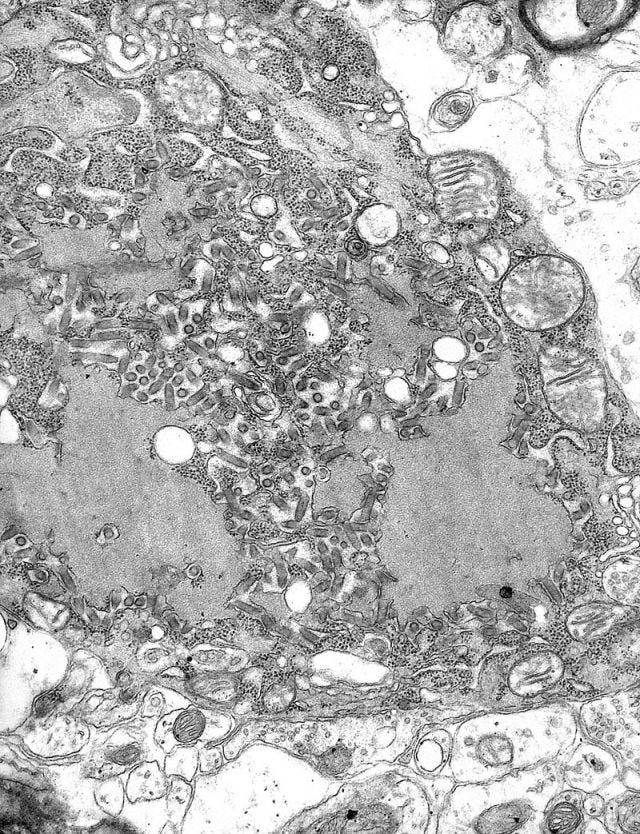

To begin, I researched everything I could on getting a dog or cat into the UK. I started with the basic customs and health requirements. Almost all the rules concern keeping this ugly little thing out of Europe:

The rabies virus